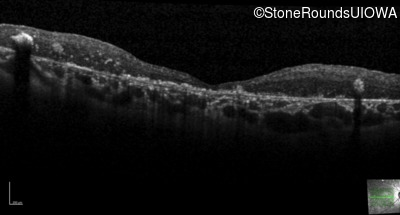

Optical Coherence Tomography - Left - 20/250 sc

Exemplar / OCT Stack